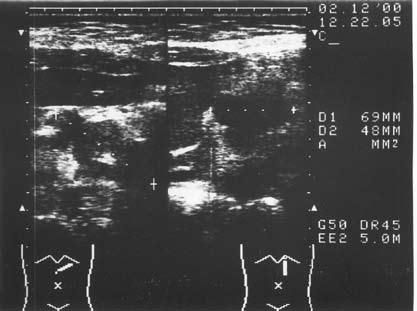

К сожалению, и специальные методы не во всех случаях позволяют решить рассматриваемую дифференциально-диагностическую задачу. Так, исследование крови больного на карбогидратный антиген (СА19-9) и раковый эмбриональный антиген (РЭА) дает отчетливо положительный ответ лишь при достаточно больших размерах опухоли, часто в неоперабельных случаях. Исследование ПЖ с помощью ультразвука или на компьютерном томографе дает увеличение размеров железы, в особенности ее головки, и при ХП, и при раке, а также выявляет очаговые образования тех или иных размеров, причем для рака более характерно одиночное гипоэхогенное образование, а при ХП поджелудочная железа чаще изменена диффузно, она гиперэхогенна (более плотная), содержит множественные кальцификаты (см. рис. 137–139), хотя точно дифференцировать характер очагов удается далеко не во всех случаях. Трудности дифференциальной диагностики ХП и рака ПЖ по данным УЗИ и КТ иллюстрируют рисунки 142–145.

Рис. 142. Ультразвуковое исследование. Рак головки ПЖ. На снимке видна гипоэхогенная бугристая раковая опухоль 5x4 см (1)